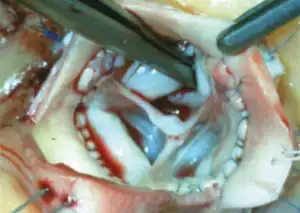

CT of the chest. Coronal (left) and axial (right) views demonstrating pathologic dilatation of the aortic root and ascending aorta. On the axial image, a dissection plane is noted in the aortic root.

Degeneration of pulmonary autograft and aortic dissection extending into the non-coronary sinus.

Before the operation, preparations include transthoracic echocardiography and measurements of the ascending aorta and the pulmonary valve.[10] Under general anaesthesia, the chest is cut open in the midline.[5] The heart and aorta are exposed before the heart is temporarily stopped and its function taken over cardiopulmonary bypass.[5] Subsequent steps include removing the diseased aortic valve and mobilizing the coronary arteries, followed by harvesting and preparing the person's own healthy pulmonary valve, before implanting it within the left ventricular outflow tract, the exit of the left side of the heart (where the aorta begins).[2][10] Then the coronary artery is reimplanted, before the pulmonary homograft is implanted in the right ventricular outflow tract, the exit of the heart's right side (where the pulmonary artery begins).[2][10] The pulmonary autograft is joined with the ascending aorta.[2][10]